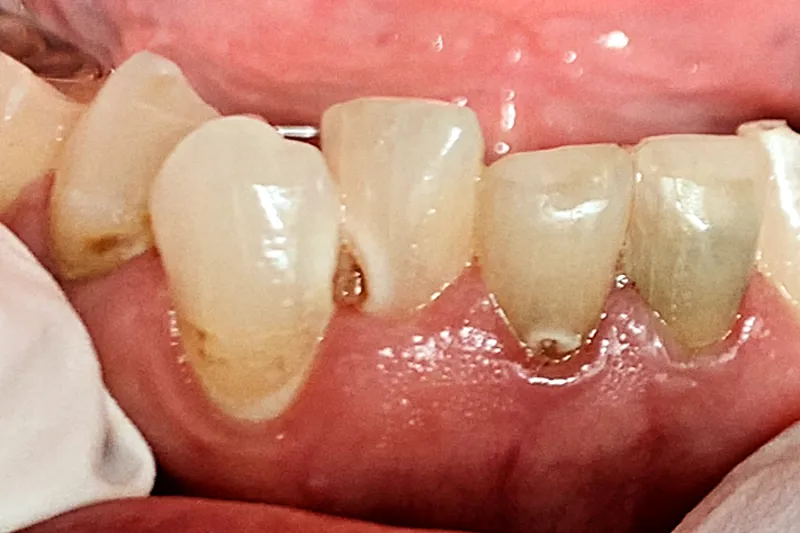

Patienttilfælde – Patienttilfældet omhandler en 69-årig kvinde, der får problemer med rygsmerter og herefter udvikler en række følgesygdomme, der fører til polyfarmaci. Sidstnævnte fører til udtalt xerostomi og hyposalivation, orale gener og sygdom, vægttab, social isolation, nedtrykthed, svækkelse og forringet livskvalitet.

Case study – This case describes a 69-year-old woman who develops problems with back pain and then develops a series of comorbidities that lead to polypharmacy. The latter results in pronounced xerostomia and hyposalivation, oral discomfort and disease, weight loss, social isolation, depression, weakness, and reduced quality of life.